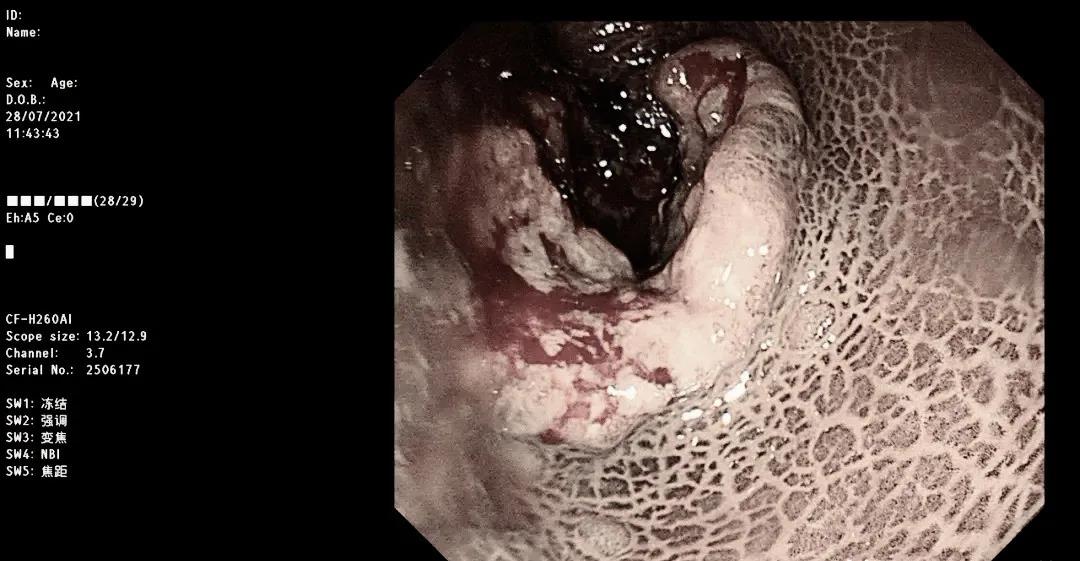

镜下可见

检查结论:结肠黑变病、直肠癌

上图:结肠黑变病